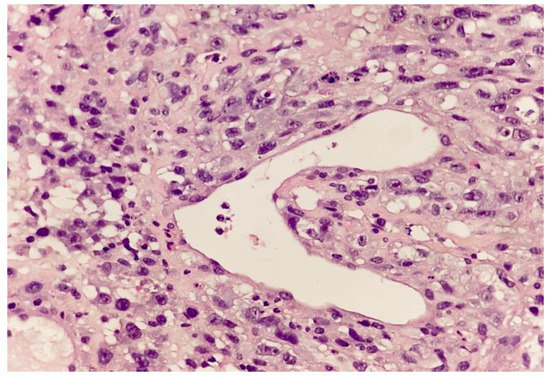

2. Case Report and Evolution